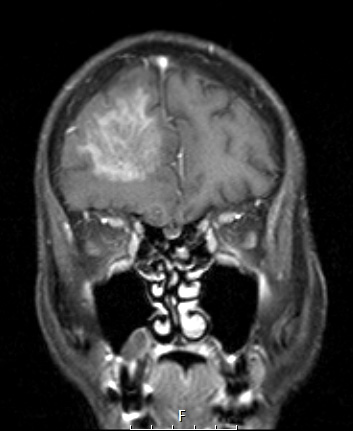

The T1-weighted exam with contrast is shown in coronal orientation.